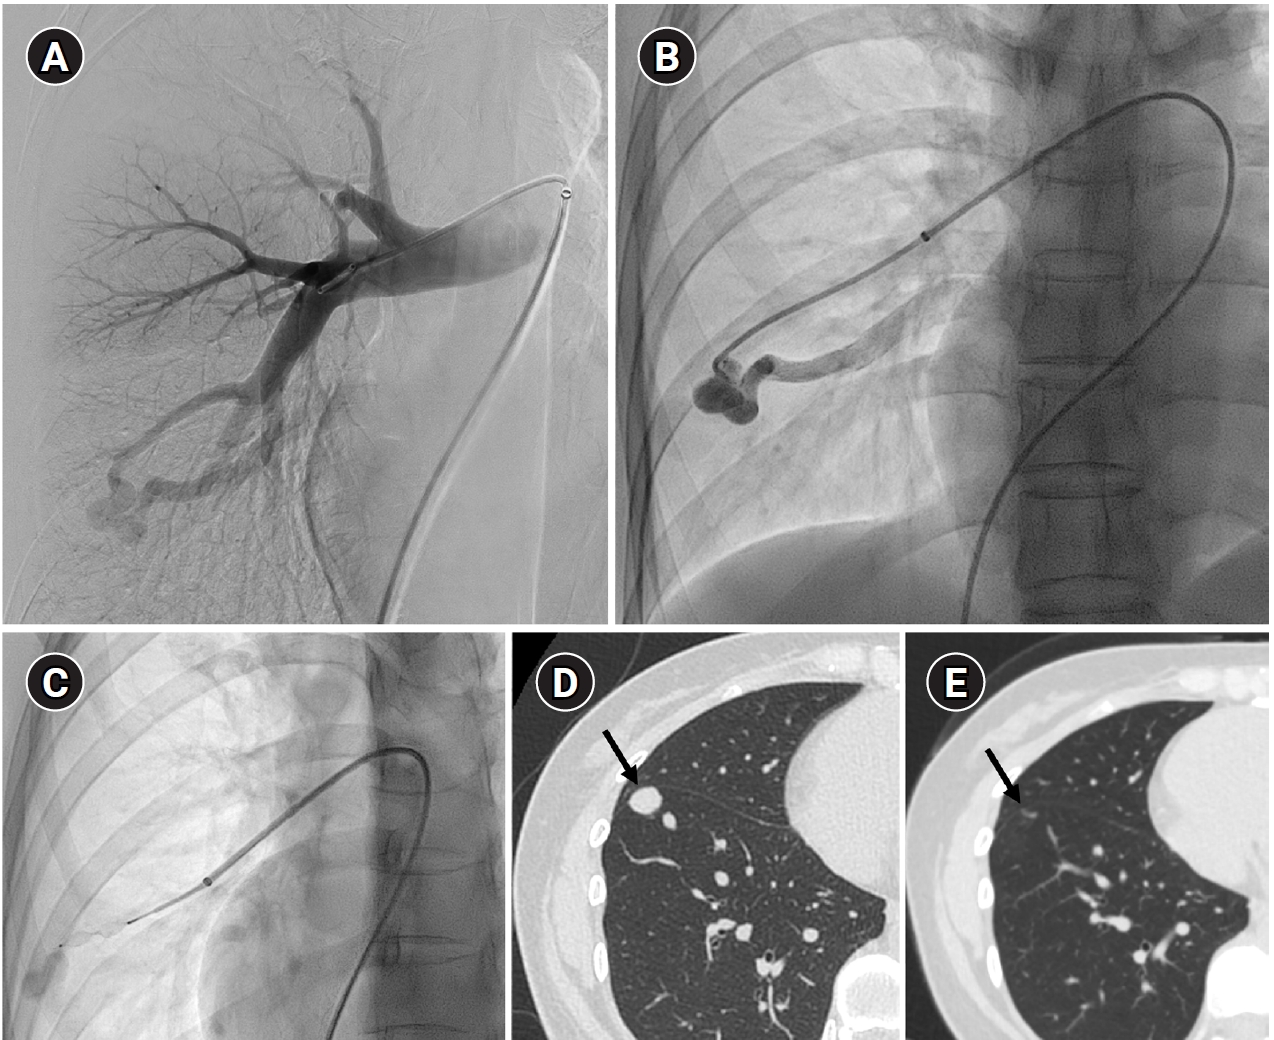

Example of a patient showing reperfusion after pulmonary arteriovenous malformation (PAVM) embolization using an Amplatzer vascular plug type IV (AVP 4). (A) Angiography of a simple-type PAVM in the right lower lobe accessed with a 5-Fr catheter. (B) Early pulmonary arterial phase image from a diagnostic angiography performed three years later due to suspected reperfusion on follow-up computed tomography, showing that the pulmonary vein is not visible distal to the AVP 4 (indicated by the arrow). (C) Delayed phase image confirming the pulmonary vein, marked by dashed arrows, which corresponds to the venous sac and draining vein seen in (A), now reduced in size. (D) A typical example of reperfusion shown on angiography using a microcatheter in an adjacent pulmonary artery, illustrating multiple newly formed tortuous collaterals leading to the draining vein (marked by dashed arrows). In this patient, additional AVP 4 embolization was performed at the tip of microcatheter (black arrow). However, draining vein size persisted even after additional treatment (not shown).

Fig. 7. Example of a patient showing reperfusion after pulmonary arteriovenous malformation (PAVM) embolization using an Amplatzer vascular plug type IV (AVP 4). (A) Angiography of a simple-type PAVM in the right lower lobe accessed with a 5-Fr catheter. (B) Early pulmonary arterial phase image from a diagnostic angiography performed three years later due to suspected reperfusion on follow-up computed tomography, showing that the pulmonary vein is not visible distal to the AVP 4 (indicated by the arrow). (C) Delayed phase image confirming the pulmonary vein, marked by dashed arrows, which corresponds to the venous sac and draining vein seen in (A), now reduced in size. (D) A typical example of reperfusion shown on angiography using a microcatheter in an adjacent pulmonary artery, illustrating multiple newly formed tortuous collaterals leading to the draining vein (marked by dashed arrows). In this patient, additional AVP 4 embolization was performed at the tip of microcatheter (black arrow). However, draining vein size persisted even after additional treatment (not shown).

Long-term follow-up after treating PAVMs is needed to detect newly developed PAVMs and to identify persistence or recurrent flow [10,11]. Treatment failure in PAVMs can be classified as recanalization and reperfusion. Recanalization refers to the reopening of blood flow through spaces between the previously placed embolic material (Fig. 6). Reperfusion, on the other hand, occurs when blood flow from an adjacent pulmonary artery reopens the previously embolized distal vein or venous sac (Fig. 7) [32]. As the primary follow-up modality, CT is recommended, but there are currently no specific guidelines on whether or not to use contrast enhancement [33]. It is recommended to perform an initial evaluation by CT about 6 months after PAVM embolization, and then follow-up with CT every 3–5 years thereafter (Fig. 8). In CT follow-up, the evaluation is based on the reduction rate of the venous sac or the draining vein, and the traditional criterion is that there should be at least a 70% reduction in the size of the venous sac or draining vein [34,35]. In recent studies, there have been opinions that this 70% size reduction criterion is too strict. In response, some research using angiographic-confirmed cases or time-resolved magnetic resonance angiography (TR-MRA) has proposed a 50%–60% guideline [36,37]. When using CT, repeated radiation exposure and metal artifacts from the coils can be problematic. By using metal artifact reduction techniques, it is possible to obtain clear images of the surrounding parenchyma, and this also helps in assessing parameters like the draining vein diameter reduction rate (Fig. 9) [38]. Furthermore, low-dose CT protocols may help reduce cumulative radiation exposure during repeated follow-up imaging.